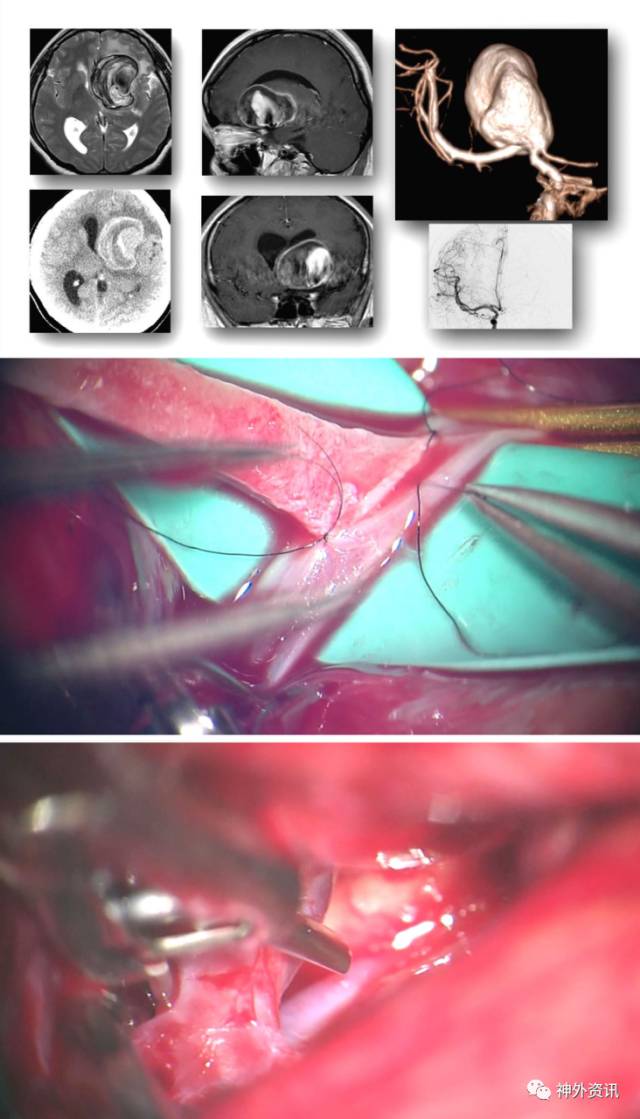

图16:一例较大的右侧ICA分叉部动脉瘤。阻断ICA后探查囊壁后极(左上图),随后开始夹闭(右上图)。伴粥样硬化斑块的动脉瘤可能要用到串联夹闭技术(下图-该患者合并有脉络前动脉动脉瘤,一并予以夹闭)。下图中的右上插图为术者在分离外侧豆纹动脉。

图17:一例钙化的巨大型动脉瘤(上图),获取桡动脉行颈外动脉-颈内动脉的高流量搭桥(中间图),随后永久闭塞脉络前动脉以远的ICA(下图)。